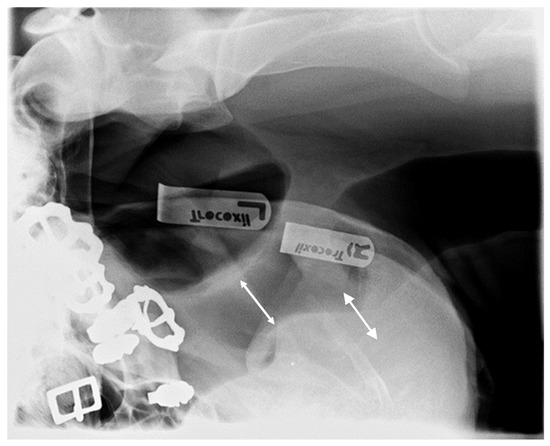

3.2.3. Pharyngeal Diameter

- Cehak, A.; Rohn, K.; Barton, A.-K.; Stadler, P.; Ohnesorge, B. Effect of head and neck position on pharyngeal diameter in horses. Vet. Radiol. Ultrasound 2010, 51, 491–497. [Google Scholar] [CrossRef]

- Go, L.; Barton, A.K.; Ohnesorge, B. Objective classification of different head and neck positions and their influence on the radiographic pharyngeal diameter on sport horses. BMC Vet. Res. 2014, 10, 118. Available online: http://www.biomedcentral.com/1746-6148/10/118 (accessed on 2 February 2023). [CrossRef] [PubMed]